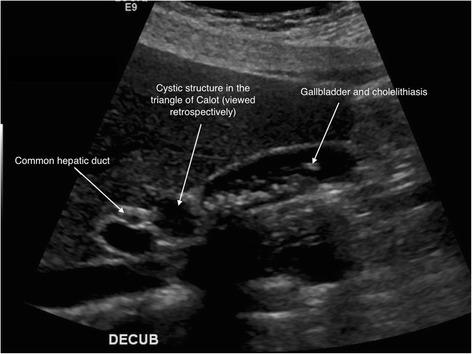

Ciliated foregut cysts are rare anomalies arising from remnants of aberrant embryological development. Around 100 reports on the presence of these congenital masses in the tracheobronchial tree, mediastinum, liver, pancreas and, rarely, the gallbladder have been described. In this article, the case of a 33-year-old woman, who was operated for a laparoscopic cholecystectomy, is presented. During the dissection of the triangle of Calot, a cystic mass, attached to the common hepatic duct, was discovered incidentally. This cyst was dissected off the hepatic duct, and no communication between both structures was found. The histopathological diagnosis was consistent with a ciliated foregut cyst. The postoperative course was uneventful. After reviewing the literature on this pathological entity, we found that this is the first report of a ciliated foregut cyst that is located in the triangle of Calot and found separate from the biliary structures, the gallbladder and the liver. We present a review of the literature on this entity, discussing diagnostic measures and therapeutic options.

纤毛前肠囊肿是一种罕见的异常情况,由胚胎发育异常的残留物引起。关于这些先天性肿物出现在气管支气管树、纵隔、肝脏、胰腺以及罕见的胆囊中的报道约有100例。本文介绍了一名33岁接受腹腔镜胆囊切除术的女性病例。在解剖胆囊三角时,偶然发现一个附着于肝总管的囊性肿物。将该囊肿从肝管上剥离,未发现两者之间有连通。组织病理学诊断与纤毛前肠囊肿相符。术后过程顺利。在查阅关于这一病理实体的文献后,我们发现这是首例位于胆囊三角且与胆道结构、胆囊和肝脏分离的纤毛前肠囊肿的报道。我们对该实体的文献进行了综述,讨论了诊断措施和治疗选择。